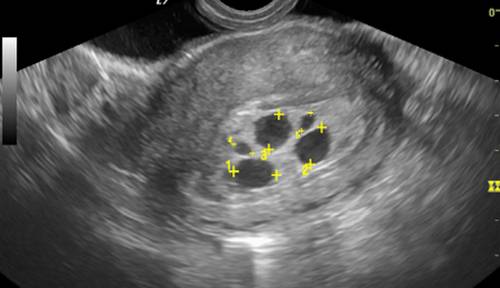

Чаще всего сформированное плодное яйцо на ранних сроках располагается в верхней части маточной полости. Оно имеет круглую или овальную форму и темно-серый, почти черный цвет с четкими границами. На этом этапе размеры эмбриона еще очень маленькие, поэтому его можно обнаружить только с помощью ультразвукового исследования.

Нередко во время УЗИ обнаруживают два плодных яйца. В таком случае врач подтверждает наличие двойни. Многоплодная беременность возникает, когда одновременно оплодотворяются две или более яйцеклетки или развивается две зиготы из одной яйцеклетки. В этом случае плодное яйцо при делении может образовать одну или две плаценты.

| Форма плодного яйца | Очертания плодного яйца на УЗИ. | Округлая или овальная. |

| Локализация плодного яйца | Место прикрепления плодного яйца в матке. | В полости матки. |

С помощью ТА-исследования плодное яйцо можно обнаружить на 5-й акушерской неделе, тогда как ТВ-скрининг позволяет выявить его уже на 4-й неделе. Первое обследование дает возможность увидеть зародыш с 5-й недели, а второе – с 6-й недели.

Для оценки размеров и роста как плодного яйца, так и эмбриона важны такие параметры, как СВД (средний внутренний диаметр плодного яйца) и КТР (копчико-теменной размер зародыша). Первый показатель демонстрирует размеры плодного яйца в миллиметрах по неделям. Этот параметр может изменяться, а для более точного определения срока беременности используется КТР. При этом исследовании возможна ошибка в пределах 3 дней в обе стороны. Обычно его проводят до 12-й недели беременности.